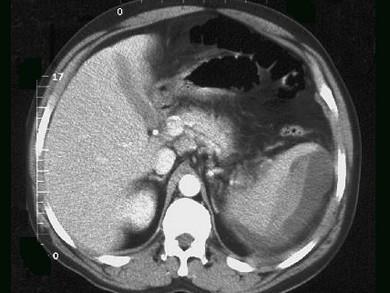

问题 男,54岁,外伤后十余天,左季肋区疼痛、肿胀。CT检查如图,最佳的诊断是 ( )

选项 A、脾梗死 B、脾扭转 C、脾包膜下血肿 D、脾挫裂伤 E、脾破裂实质内血肿

答案 C